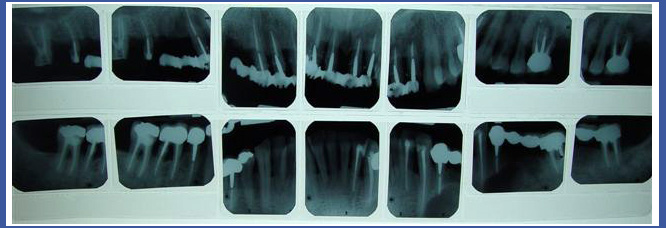

3. Статусный снимок

Это снимок, который выполняется в рентгеновском кабинете и состоит из 14-18 периапикальных снимков, включающих все зубы, которые есть во рту.

Статусный снимок обычно выполняется в качестве диагностической меры в отношении людей, которые проходят/прошли реабилитацию полости рта; людей, у которых существует проблема отслоения костей и десен – снимок позволяет увидеть высоту кости, которая держит зубы.

Часто стоматолог попросит Вас принести статусный снимок, который включает также и снимки прикуса.

4. Параллельный статусный снимок: :

Во многих случаях стоматолог направит Вас на выполнение статусного снимка. Хотя это вообще-то серьезная вещь, а не обычный статусный снимок…

Снимок построен из 20-ти периапикальных (отдельных) снимков; к этому снимку всегда присоединяют и 4 снимка прикуса.

Для выполнения этого снимка используют более узкую пленку для передних зубов, и при выполнении каждого снимка продвигаются на один зуб, в отличие от обычного статусного снимка, при выполнении которого используется одна лента и выполняется продвижение на несколько зубов одновременно.

При выполнении статусного параллельного снимка сам снимок держится во рту с помощью чистого, эстетичного и часто даже стерильного пластикового приспособления. Луч сфокусирован и не распространяется в стороны.

Этот снимок на профессиональном языке называется «ортодонтическим» и вообще-то он как бы представляет собой «тень» зуба, но пропорционально увеличен.

Представьте себе, что Вы, выпрямившись, стоите напротив зеркала: что произойдет, если наклонять зеркало вперед или назад? Конечно, части тела будут выглядеть искаженными – короткие ноги, длинное тело и т. д. В этом и заключается разница между обычным статусным снимком и параллельным статусным снимком, выполненным правильно и точно.

Стоматологи имеют обыкновение направлять пациентов на выполнение обычного статусного снимка, потому что результат получается достаточно хорошего качества; подходит для основных реабилитационных, косметических и хирургических целей, и, если говорить честно, они не всегда осведомлены о недостатках этого вида рентгеновких снимков.

Хотя статусный параллельный снимок более дорогостоящий, но, по-моему, это вложение несомненно окупается.